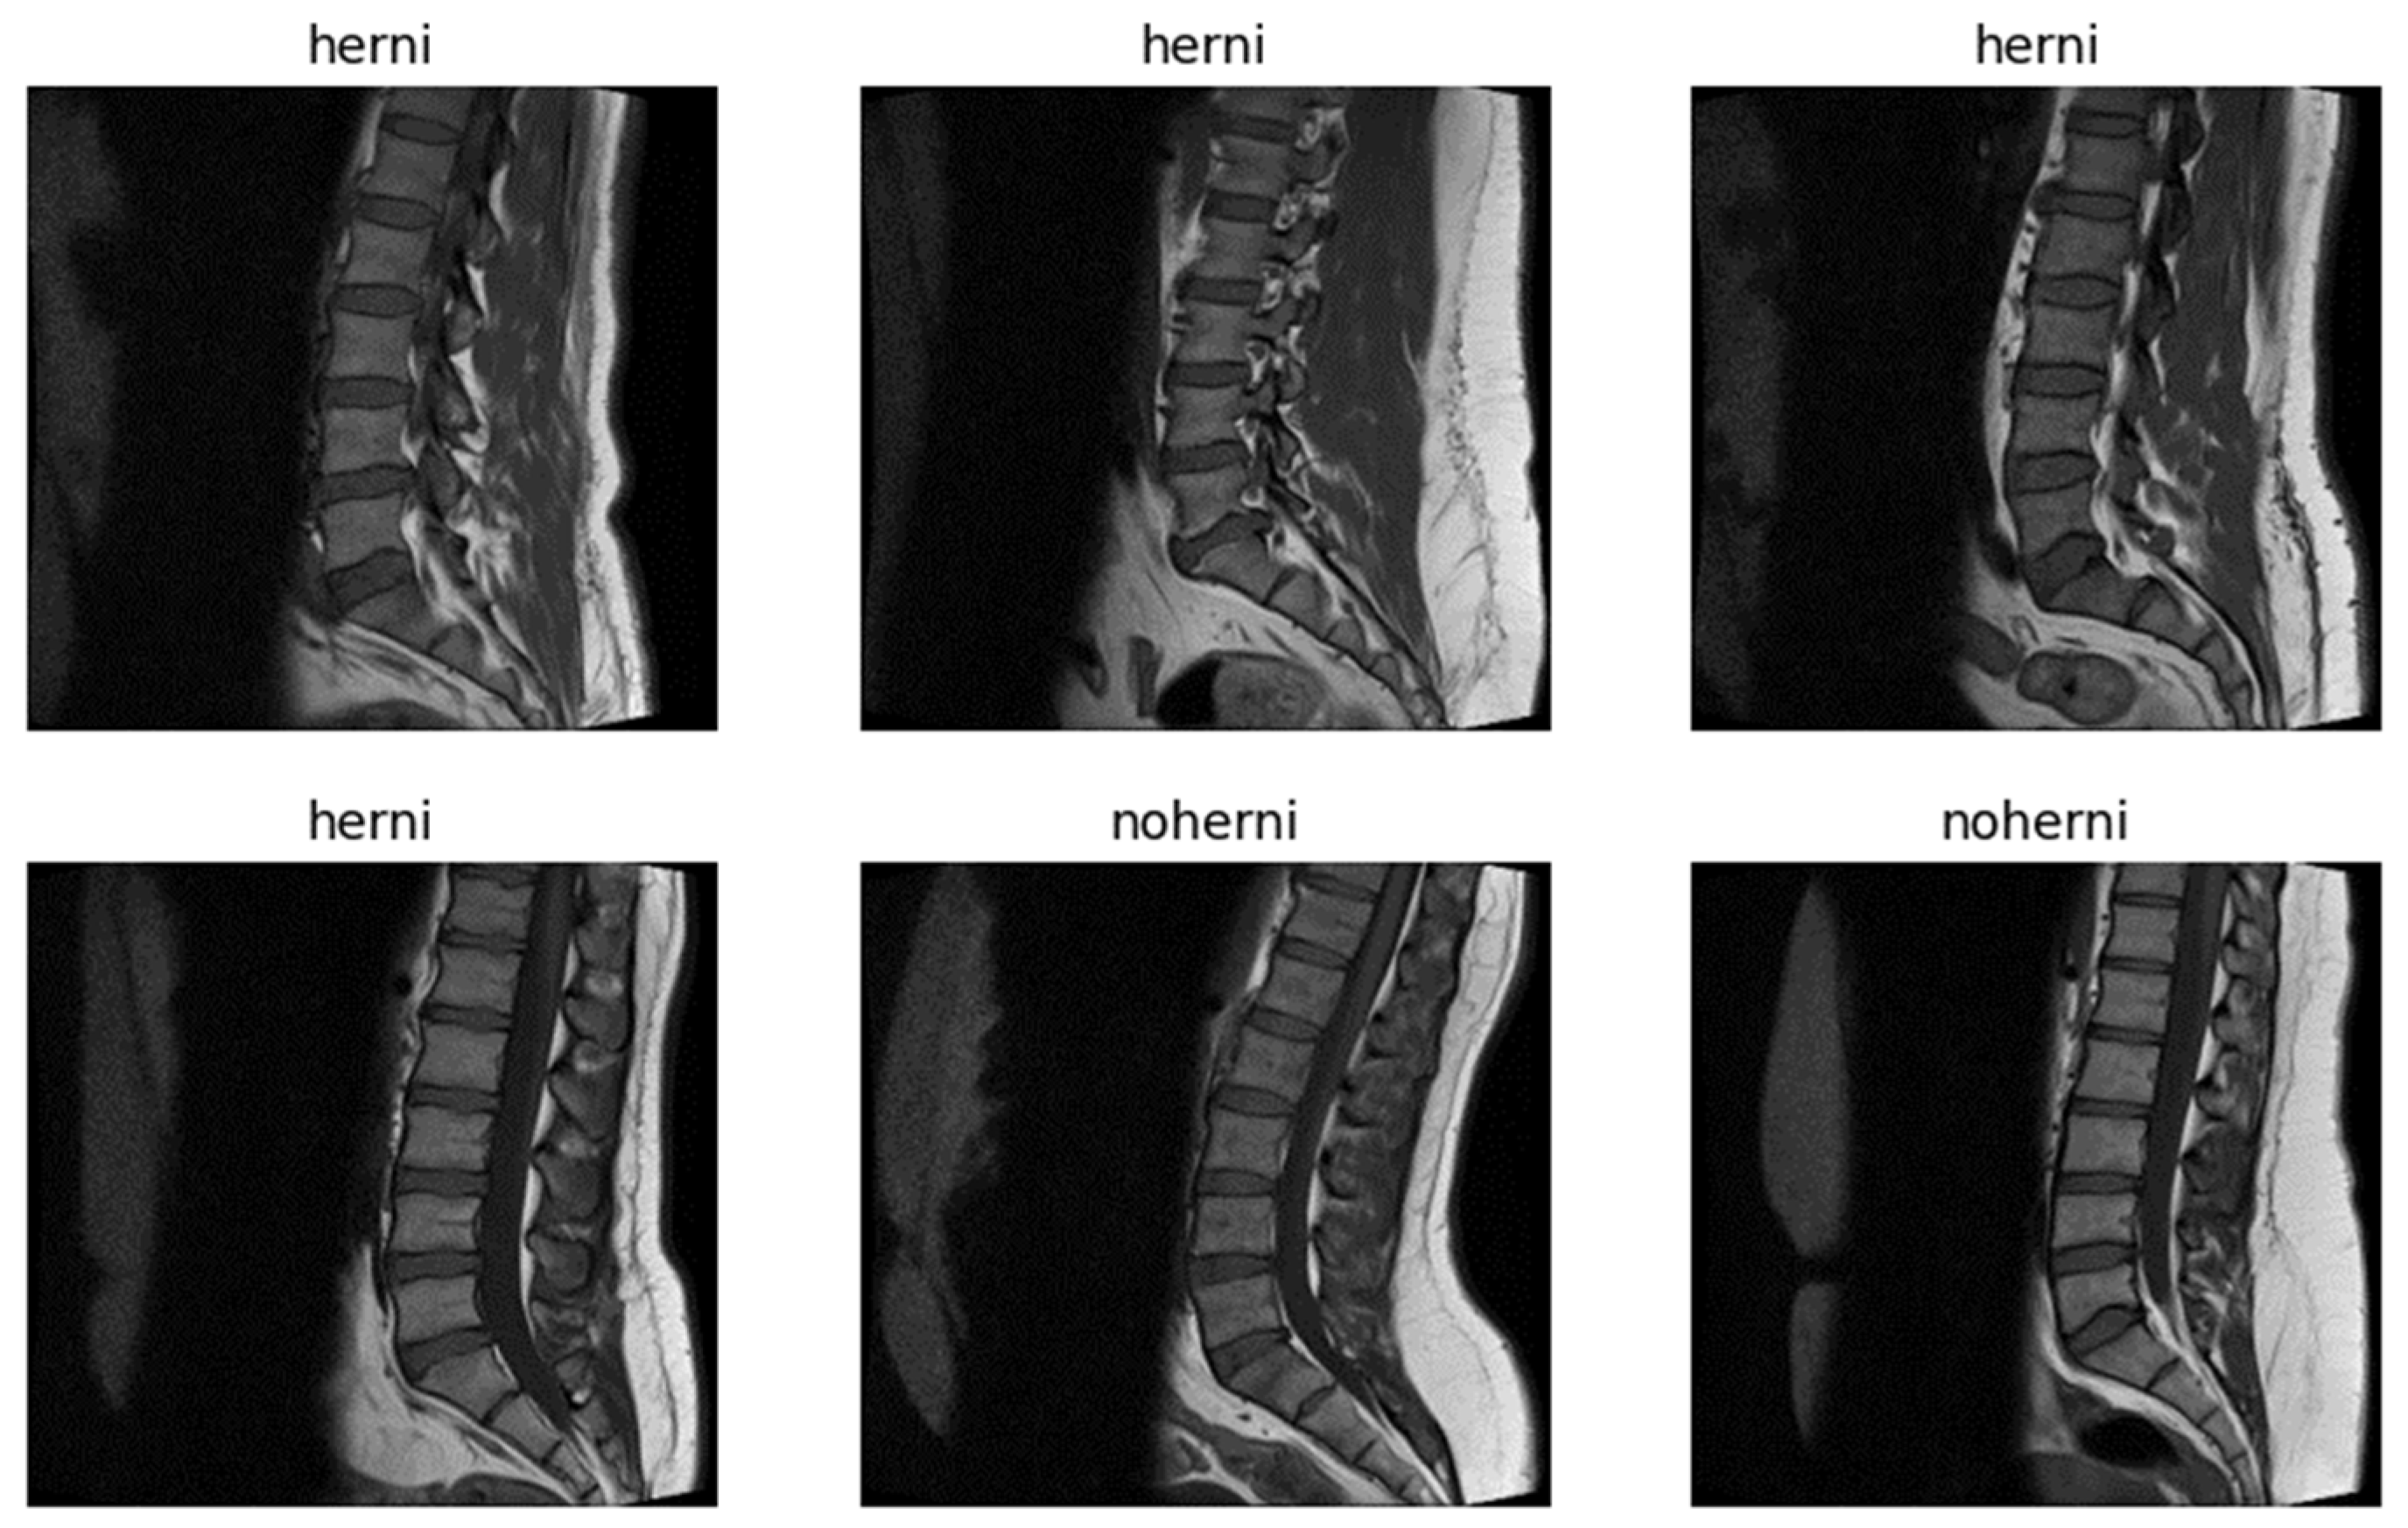

The dataset originally contained 48,345 MRI slices, most of which are 320 × 320 pixels in resolution, with a few outliers at 320 × 310 pixels. These images are stored in the IMA format—a high-precision format with 12 bits per pixel—providing a level of detail greater than that of the standard 8-bit grayscale images which are typically used in most imaging datasets [21]. The higher bit depth is particularly useful for medical images, as it enables finer details that may be essential for diagnosing subtle abnormalities, such as disc herniation. Figure 2 presents randomly selected sample images from the dataset.

For the purposes of this study, a subset of 1198 selected images was used, containing both images with and without vertebral disc degeneration. The decision to reduce the dataset was driven by several factors. First, the computational resources available for processing the data were limited, preventing use of the full dataset. Second, there were undiagnosed or mislabeled samples in the dataset, which could have compromised the quality and accuracy of the model. Third, the imbalance in the data (i.e., more hernia cases than non-hernia cases) posed a challenge and, thus, careful selection was necessary to mitigate this issue. Additionally, MRI slices that appeared distorted due to errors during the scanning process were removed from the dataset to ensure that only high-quality images were included for training. From the IMA raw data, we selected T1-weighted images to achieve improved representation of brightness and darkness characteristics.

Figure 2. Sample images from the dataset.